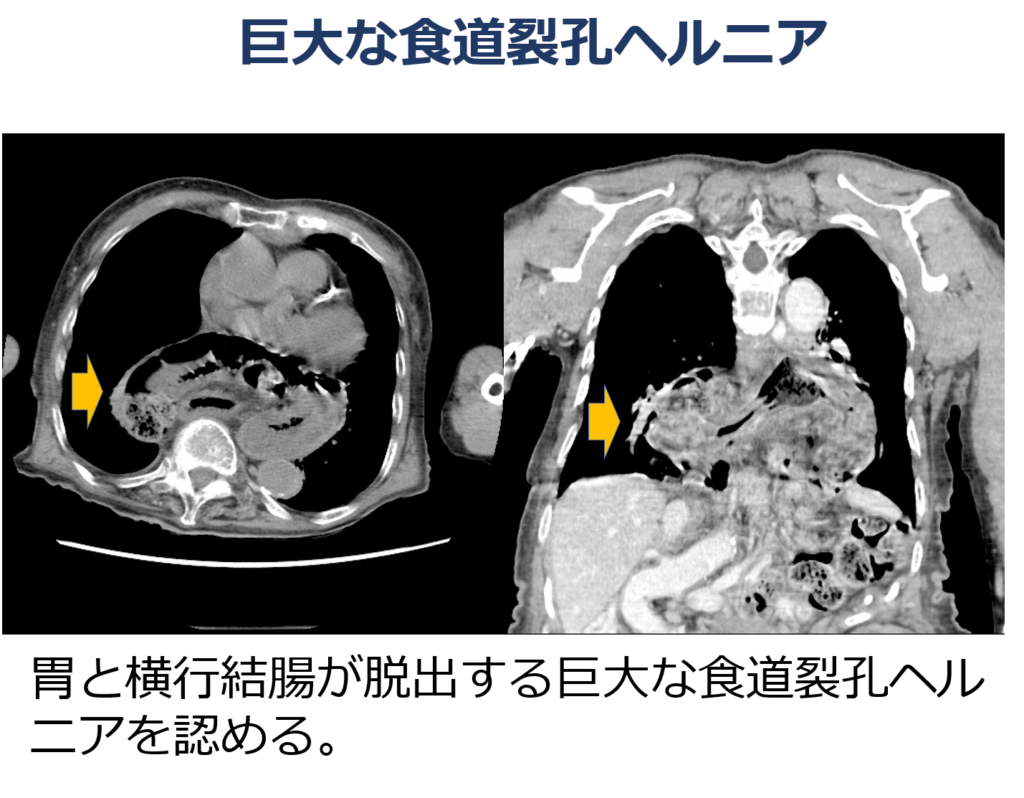

このような内科的治療で改善しにくい場合に有効な治療法が外科的治療です。また、近年の日本ではご高齢の方の人口が増加しており、年齢とともに増加するとされる食道裂孔ヘルニアを有する方が増加しています。ご高齢の方では大きな食道裂孔ヘルニアを有する方が多く、これに伴い手術件数が増加していることが報告されています(図1、2)。

当科では、2017年より食道裂孔ヘルニアに対する腹腔鏡手術を導入し、現在までに450件を超える手術経験があり、2019年度から2023年度の5年間連続で日本で最も多く手術を行なっています(図3)。約半数の方が、巨大な食道裂孔ヘルニアを有する方に対する手術で、30%以上の方が大阪府外から当院へ手術を目的に来院された方です。さらに、当院では腹腔鏡手術の成績安定のために、日本内視鏡外科学会が認定する技術認定医が4人在職し安全に食道裂孔ヘルニアに対する手術を行っています。